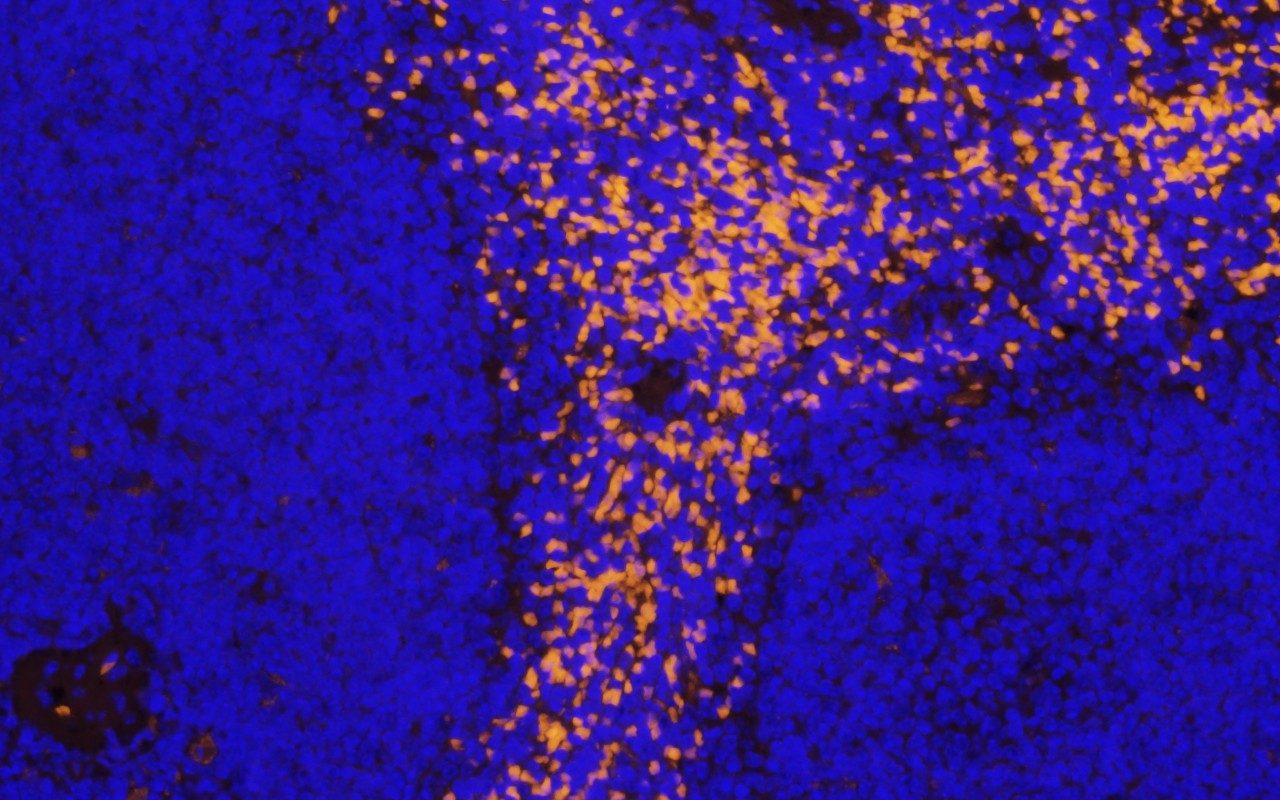

- Multiplex Immunofluorescence

The specialized techniques performed in the Research Histology Core Laboratory (RHCL) include automated and manual IHC staining, cell line processing, tissue microarrays and accommodating special projects upon request. Immunostaining is done on both human and animal tissues with a required preliminary consultation of the protocol. Staining is performed on the Leica Bond RX stainer. Tissue Micro Arrays (TMA) are constructed on the Beecher Automatic or Manual Tissue Arrayers. Cell lines are meticulously processed in such a way that 95% of the time no cells are lost. In the future, the RHCL is working to offer other molecular techniques such as in situ hybridization, FISH and fluorescent staining.

The Research Histology Core Laboratory (RHCL) offers Digital Pathology and Imaging services. Digital Pathology includes Quantification and Annotation which will be offered in conjunction with slide scanning using our Leica Aperio AT2 Slide Scanner. Slide Scanning will provide automated quantification for accurate evaluation of complex staining patterns which allows researchers and clinicians to interpret tissue staining.

The Slide Scanning service offers high quality and high resolution images for researches to use for the projects. Benefits include: images that can be used for presentations, collaborations from anywhere, fast and easy interpretations and quantitative evaluation.